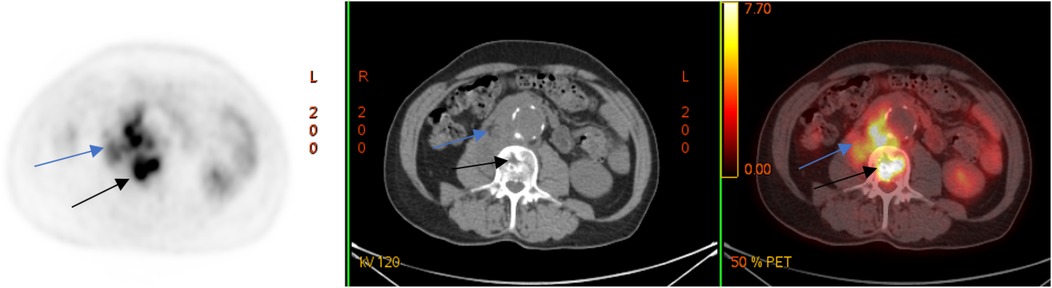

A laboratory examination on 12 March 2024 showed elevated levels of C-reactive protein (CRP, 26.62 mg/L) and leukocytes 6.4 × 109/L. To clarify the diagnosis, a couple of days later, the patient underwent positron emission tomography combined with computed tomography (PET/CT) with the use of 18F-fluorodeoxyglucose (18F-FDG), which revealed a metabolically active retroperitoneal infiltrate extending to the right psoas muscle and the L2–L3 vertebral bodies (Figure 2).

Figure 2

18F-FDG PET/CT (axial slices) demonstrates the presence of a metabolically active retroperitoneal infiltrate with extension to the right m. psoas (blue arrows) and lumbar vertebral bodies (black arrows).